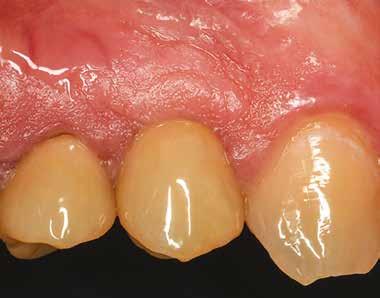

Preoperatív helyzet

Egy fiatal páciens jelentkezett nálunk, akinek eltörött a szabad véggel rendelkező hídja (1. ábra). A hiányzó, első premoláris fog esetén implantációs pótlást javasoltunk. A csontállomány értékeléséhez CBCT-vizsgálatot végeztünk, és az elemzéséhez NNT Viewert (NewTom) használtunk, és copaSKY 4×10 mm-es (bredent medical) implantátumot választottuk a fog pótlásához

1. ábra: Műtét előtti fogászati panorámafelvétel, amelyen a hiányzó felső állcsont jobb első premolárisát és a szabad véggel rendelkező hidat láthatjuk. — 2. ábra: Az implantátum méreteinek megtervezése CBCT-vel. 3. ábra: Bukkális lágyrészdefektus. — 4. ábra: A biológiai szélesség értékelése a vertikális lágyszövetvastagság alapján. 5. ábra: Palatinális „tekercslebeny” – Palatal roll flap. — 6. ábra: Bredent medical copaSKY 4x10 implantátumbeültetés. 7. ábra: Szubkresztális implantátumbeültetés a várható biológiai szélességnek megfelelően.

(2. ábra). A lágyszövetek értékelése Seibert szerinti I. osztályú csontdefektust állapított meg (3. ábra), ezért a beavatkozáskor palatinális „tekercslebenyt” preparáltunk (palatal roll flap), és implantációt végeztünk, hogy kompenzálni tudjuk a bukkális lágyszövet-behúzódást. Megmértük a vertikális lágyszövetvastagságot, és úgy terveztük, hogy a szubkresztális implantátum beültetése összhangban legyen a biológiai szélesség kialakulásával a transzgingivális gyógyulási periódus alatt (4. ábra)